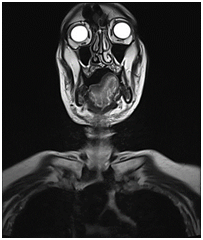

A 70 years old male patient presented to the emergency department with stridor and dysphagia of 3months duration. Patient was examined by fiber optic nasopharyngoscope which revealed supra-glottic mass to the left side with restricted mobility of the left vocal cord. Patient was admitted and submitted for urgent tracheostomy. MRI neck with contrast was done and revealed a Supraglottic mass measuring about 2cm X 1.5cm, partially occluding the airway and showing enhancement post gadolinium injection. It is appearing isointense in T1 and T2-weighted images with mildly enlarged vocal cords (Figure 1–3).  Panendoscopy was performed on 18/02/2018 and revealed a mass occupying the post cricoid area, pyriform fossa, supraglottic and the lateral pharyngeal wall. Base of the tongue, tonsils, right side of the larynx and the posterior pharyngeal wall were free.

Figure 3 MRI neck with contrast, coronal cut, showing mildly enlarged vocal cords.